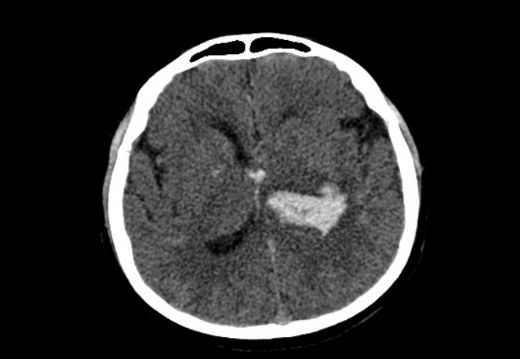

Çocuklarda beyin kanaması, çeşitli nedenlerle meydana gelebilen ciddi bir sağlık sorunudur. Bu durum, çocukların beyin dokusunun zarar görmesine ve yaşamı tehdit eden komplikasyonların ortaya çıkmasına yol açabilir. Beyin kanaması, kafatası içindeki kan damarlarının yırtılması veya sızdırması sonucu meydana gelir ve belirtileri, kanamanın türüne, yerine ve şiddetine bağlı olarak değişiklik gösterir. Beyin Kanaması Türleri Beyin kanamaları, çeşitli tiplere ayrılmaktadır. Bu türler arasında en yaygın olanları şunlardır:

Her bir kanama türü, farklı nedenlere, belirtilere ve tedavi yöntemlerine sahiptir. Belirtiler Çocuklarda beyin kanaması belirtileri, durumun ciddiyetine göre değişiklik gösterebilir. Aşağıdaki belirti ve semptomlar, beyin kanaması yaşayan bir çocukta gözlemlenebilir: